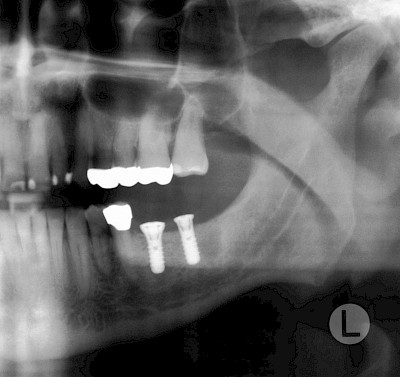

Implantate sind künstliche Zahnwurzeln – meist aus Titanlegierungen, selten auch aus keramischen Werkstoffen. Gehen Zähne verloren werden diese Implantate in den Kiefer eingebracht. Nach einer gewissen Einheilzeit (3-6 Monate) im Knochen wird zunächst für ein bis zwei Wochen das Zahnfleisch im Bereich die Durchtritts-Stelle "geformt" und in der Folge der sogenannte Aufbau (Abutment) aufgeschraubt. Der Aufbau erlaubt dann die Befestigung einer Krone, Brücke oder Zahnprothese.

In diesen Fällen kann die Planung mittels verschieden aufwendiger Röntgen-Techniken (Übersichtsaufnahme, DVT) ggf. unter Zuhilfenahme speziell angefertigter Planungsschablonen sinnvoll sein.